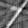

Refer to caption

Figure 1: Schematic of sparse-view imaging setup and reconstruction framework augmented with out-of-distribution detector.

An accurate and automated CT reconstruction pipeline is a sought-after target for many clinical and industrial practices. The aforementioned diffusion models appear to be aligned with this objective but necessitate an OOD detection mechanism, either to prevent reconstructions in situations that surpass the model’s generalization capacity or to purposely inspect abnormalities. Despite the extensive literature demonstrating the potential of diffusion models as unsupervised inverse problem solvers and OOD detection tools separately, to the best of our knowledge, this will be the first study at their intersection. Moreover, from a broader point of view, there is a gap in the literature regarding the applicability of the reconstruction-based OOD detection paradigm to inverse problems, where the inputs are incomplete in some manner. As far as we know, the recent study [16] stands as the only research employing a reconstruction-based OOD detection approach for image reconstruction, where the models are trained in supervised manner and OOD detection task is approached from an uncertainty estimation perspective. So, the main focus of this paper is exploring the use of diffusion models for OOD detection in unsupervised sparse-view CT reconstruction. Our goal is to address questions such as: Can a diffusion model trained to capture the prior distribution for a sparse-view CT reconstruction task be also utilized for OOD detection as shown in Fig. 1? Given the in-distribution dataset of full-view images, how well can this model generalize to the distribution shift caused by the sparse-view mappings of in-distribution images? Does conditioning on the measurements aid or hinder the OOD detection process? How should we redefine the notion of reconstruction error, given that its usual definition is impractical in the case of sparse-view tomography? We believe that the answers to these questions are crucial for better understanding and may provide insights for future research directions on reliable CT reconstruction pipelines. We conduct all experiments on MNIST images [17] within a one-class experimental setup. In this setup, the diffusion model is trained on one digit, treating all other digits as OOD.